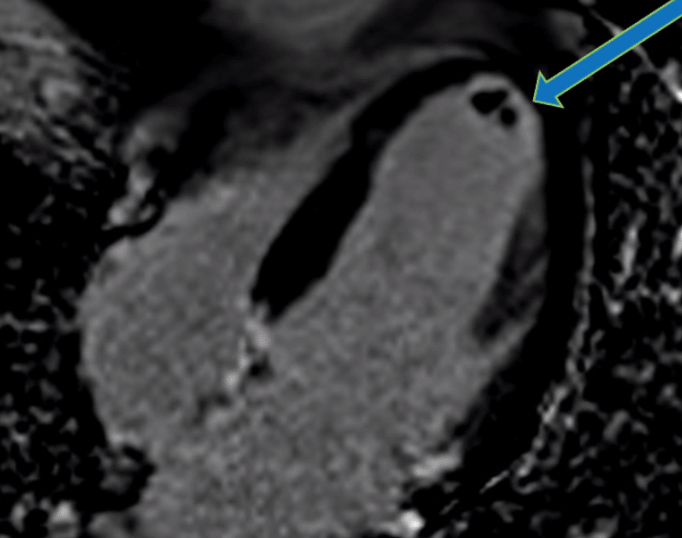

Nach aktuellem Forschungsstand gilt die Magnetresonanztomographie des Herzens (Kardio-MRT oder auch Herz-MRT) aktuell als die genaueste Methode zur Beurteilung der Morphologie („Herzarchitektur“) und Funktion („Herzkraft“) des Herzens und des Herzmuskels.

Die Kardio-MRT ist mittlerweile als Referenzstandard zur Beurteilung der Funktion und der Durchblutungsmessung wissenschaftlich und klinisch (europäische Leitlinien der ESC) anerkannt und somit zuverlässig verwendbar.